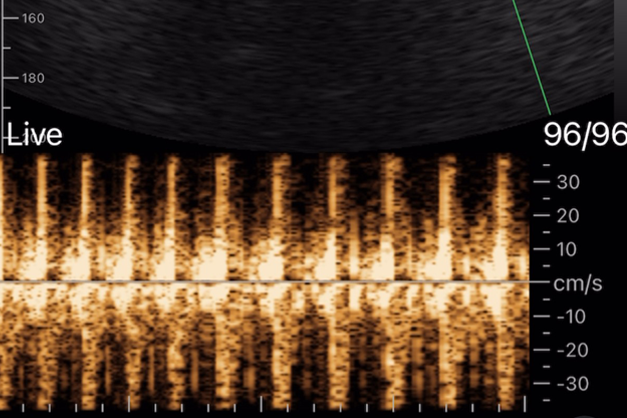

赤ちゃんが見える、心音も聞こえる